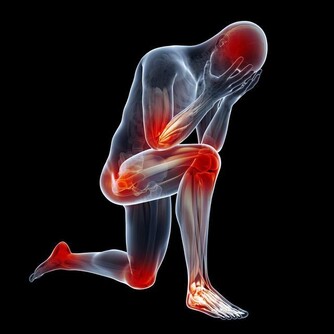

據臨床觀察,白血病患者的常見症狀包括體重異常減輕、疲倦乏力、呼吸急促、淋巴結腫大、胃部腫脹、發熱盜汗、骨痛或關節痛、頻繁反复地感染等。而患者也會感到皮膚組織瘙癢難忍,或是非常容易造成淤青或出血。如果發現自己的皮膚有類似的情況出現,一定要立即檢查,因為許多人都會忽視自己皮膚上的小問題。

隨著病情惡化,患者逐漸會感到自己的骨頭在隱隱作痛,骨骼似乎非常脆弱,而且會感到疲倦乏力,刷牙時也會引起牙齦出血,女性患者在經期間的排血量也會異常增多。